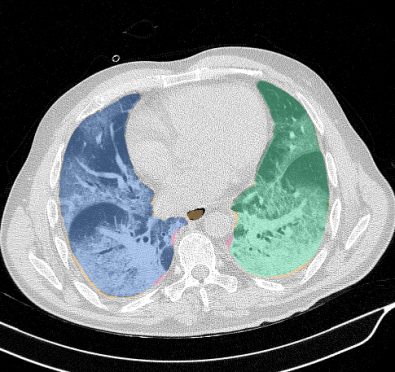

Lobar segmentation results for the proposed method and PTK are shown in Figure 5 for right lungs and Figure 6 for left lungs. For each image in the COVID-19 dataset (133 images in total), the lobar segmentation result was used to extract the amount of poor aeration () and consolidation () in each lobe. Common phenotypes of COVID-19 affected lungs were identified by hierarchical clustering over the fraction of poorly aerated and consolidated tissue in each lobe. Dendrographic analysis in Figure 7 reveals four primary clusters of patients that were identified by the hierarchical clustering: (a) mild loss of aeration primarily in the two lower lobes without consolidation; (b) moderate loss of aeration focused in the two lower lobes with or without consolidation in lower lobes; (c) severe loss of aeration throughout all lobes with or without consolidation; and (d) severe loss of aeration and consolidation throughout all lobes.

Lung segmentation results for the polymorphic and nonpolymorphic models are shown in Figure 3. Quantitative evaluation of lung segmentations was performed on CT images by comparing the segmentations to ground truth manual segmentations. The Dice coefficient was used to measure volume overlap and the average symmetric surface distance (ASSD) was used to assess boundary accuracy. The ASSD and Dice coefficient results for each of the four evaluation datasets are shown in Table 2. Overall, on the COVID-19 dataset the polymorphic model achieved an average ASSD of mm and average Dice coefficient of . By comparison, the nonpolymorphic model achieved an average ASSD of mm and average Dice coefficient of . ASSD and Dice coefficient results with respect to nonaerated lung volume fraction are displayed in Figure 4. Two-way analysis of variance revealed a significant interaction between model and nonaerated fraction for each evaluation metric, indicating that the regression coefficients with respect to nonaerated fraction were significantly different for polymorphic vs. nonpolymorphic models.

In this study, we proposed and implemented a novel polymorphic training algorithm for lung and lobar segmentation in a fully automated pipeline. The pipeline was independently evaluated on CT scans of subjects with COVID-19, lung cancer, and IPF - however, no COVID-19, lung cancer, or IPF scans were utilized for training the CNNs. Additionally, the pipeline was extensively evaluated on CT scans of patients with COPD. The COVID-19 scans are considered very challenging cases for lung and lobe segmentation. Peripheral and diffuse opacities result in little contrast at the lung boundary. In many cases, the fissure appearance was irregular due to close proximity of infection. Furthermore, these are clinical scans with some cases having slice thickness greater than 3 mm. Fissure segmentation is especially challenging on such cases. Success of the proposed algorithm on these cases lends to the generalizability of the proposed approach.